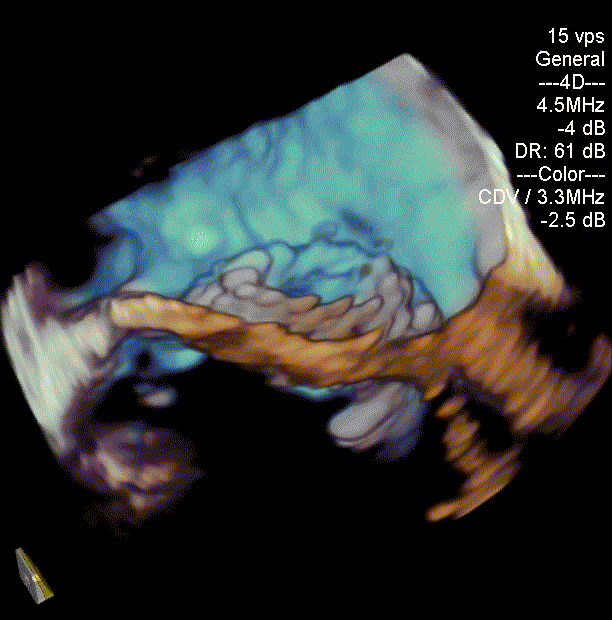

病例1(二尖瓣“瓣中瓣中瓣”):

患者男性,60岁, 2016年行二尖瓣置换术+心脏搭桥术,植入29号生物瓣一枚。后瓣膜损毁2019年经心尖途径行二尖瓣“瓣中瓣”手术,植入27# 自膨式介入瓣一枚。患者一周前无明显诱因发生活动后气喘,伴胸闷,复查心脏超声提示自膨式介入瓣损毁,瓣膜轻度狭窄伴重度关闭不全。患者合并肾衰,长期透析,既往行右侧股骨头置换,右小腿截肢。STS评分8.589%,患者病情复杂,属于常规外科再次换瓣手术高风险患者。

经过手术团队充分讨论病例资料,模拟在首次手术生物瓣环与第二次手术瓣膜内植入定位更精准的佰仁Renato®球扩式瓣中瓣,以有效治疗二尖瓣自膨式介入瓣毁损。手术按照术前讨论方案进行,过程顺利,成功植入27号Renato®球扩瓣,瓣膜植入位置理想,启闭功能表现出色。左室造影及经食道超声观察无明显瓣中及瓣周反流,平均跨瓣压差降至8.0mmHg。

球扩瓣释放

瓣中瓣植入前

二尖瓣重度反流

瓣中瓣植入后

无明显瓣中及瓣周反流